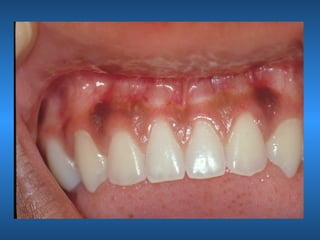

Pigmentação Melânica

• Características Clínicas